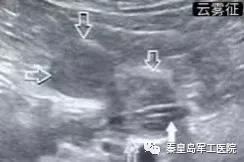

为提高危重症患者置管成功率,王秋艳主任与姚明慧护士长配合,通过床旁超声引导下成功进行鼻肠管的置入。床旁超声被喻为看得见的“听诊器”,在重症医学科的应用日益广泛。该技术利用超声优势,在床旁进行实时引导,准确通过幽门后进行肠内置管。

相比传统方法,超声引导更加安全稳定,无副作用,置管成功率高。通过超声评估胃排空功能,测量胃残余量等优势,可以尽快给足营养支持,更好的保证患者安全,有效节省人力资源。